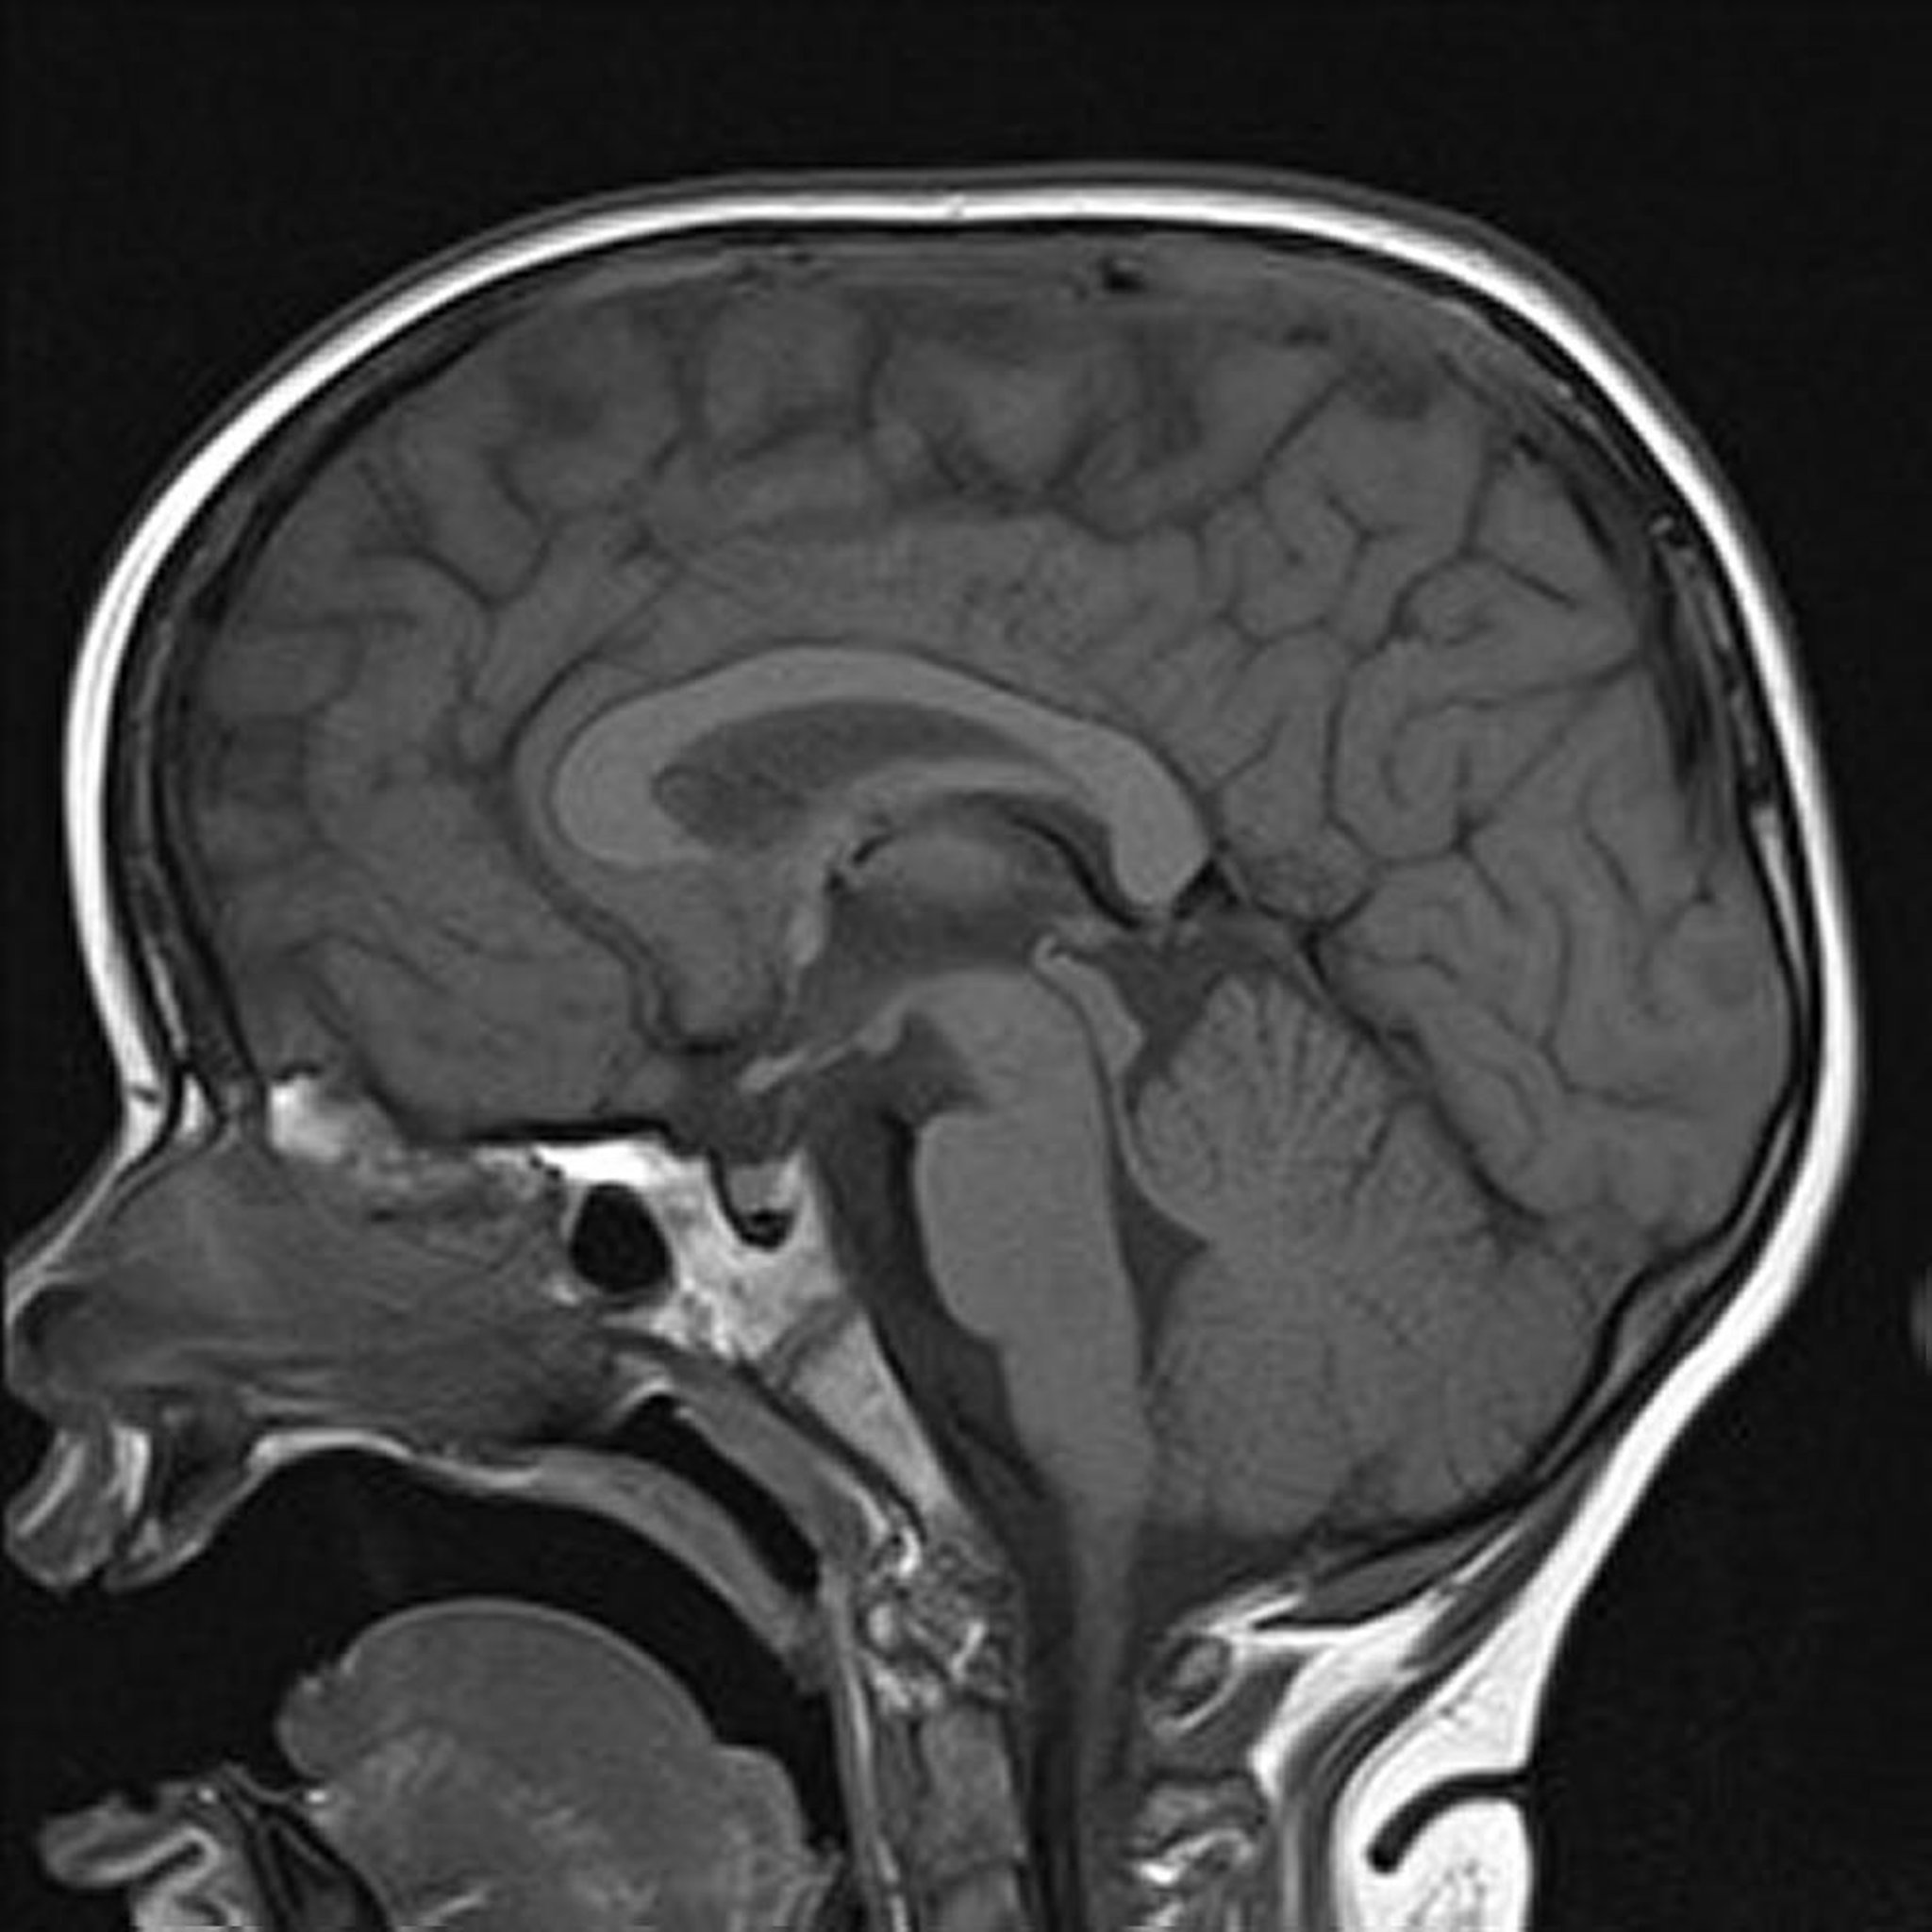

この脳のT1強調矢状断像には,正常な正中線の構造が示されている。

例えば,脂肪はT1強調像では明るく(信号強度が高く),T2強調像では比較的暗く(信号強度が低く)見える;水および液体はT1強調像では比較的暗く,T2強調像では明るく見える。T1強調像は,正常軟部組織の解剖および脂肪を示すのに最適である(例,脂肪を含有する腫瘤の確認のため)。T2強調像は,液体および異常(例,腫瘍,炎症,外傷)を示すのに最適である。臨床では,T1強調像およびT2強調像から相補的な情報が得られるため,異常の特徴を示すには両方が重要である。